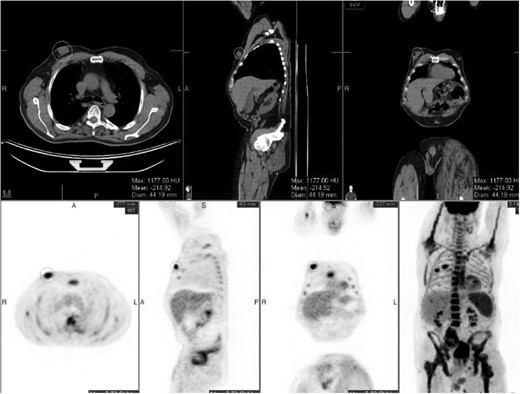

A 56-year-old male presented with a right-sided breast mass confirmed on mammogram as a 5.4 × 4.4 cm lobulated solid mass suspicious for cancer (Fig. 1). Axillary ultrasound revealed one suspicious lymph node. Core needle biopsy of the breast mass showed invasive poorly differentiated ductal carcinoma, ER+/PR+/HER+. The lymph node biopsy was negative for malignancy. Medical history was significant for hypertension and neurofibromatosis type 1. The patient noted no family history of breast, ovarian or prostate cancer; however, there was a four generation history of neurofibromatosis on his mother's side.

Right chest wall neurofibroma. Breast cancer is superior to the nipple.